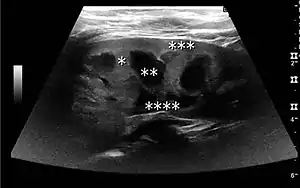

The kidney is divided into parenchyma and renal sinus. The renal sinus is hyperechoic and is composed of calyces, the renal pelvis, fat and the major intrarenal vessels. In the normal kidney, the urinary collecting system in the renal sinus is not visible, but it creates a heteroechoic appearance with the interposed fat and vessels. The parenchyma is more hypoechoic and homogenous and is divided into the outermost cortex and the innermost and slightly less echogenic medullary pyramids. Between the pyramids are the cortical infoldings, called columns of Bertin (Figure 1). In the pediatric patient, it is easier to differentiate the hypoechoic medullar pyramids from the more echogenic peripheral zone of the cortex in the parenchyma rim, as well as the columns of Bertin (Figure 2).[1]

Complex cysts can have membranes dividing the fluid-filled center with internal echoes, calcifications or irregular thickened walls. The complex cyst can be further evaluated with Doppler US, and for Bosniak classification and follow-up of complex cysts, either contrast-enhanced ultrasound (CEUS) or contrast CT is used (Figure 6). The Bosniak classification is divided into four groups going from I, corresponding to a simple cyst, to IV, corresponding to a cyst with solid parts and an 85–100% risk of malignancy.[1] In polycystic kidney disease, multiple cysts of varying size in close contact with each other are seen filling virtually the entire renal region. In advanced stages of this disease, the kidneys are enlarged with a lack of corticomedullary differentiation (Figure 7).[1]

Figure 6. Complex cyst with thickened walls and membranes in the lower pole of an adult kidney. Measurements of kidney length and the complex cyst on the US image are illustrated by '+' and dashed lines.[1] Figure 7. Advanced polycystic kidney disease with multiple cysts.[1]

Figure 7. Advanced polycystic kidney disease with multiple cysts.[1]